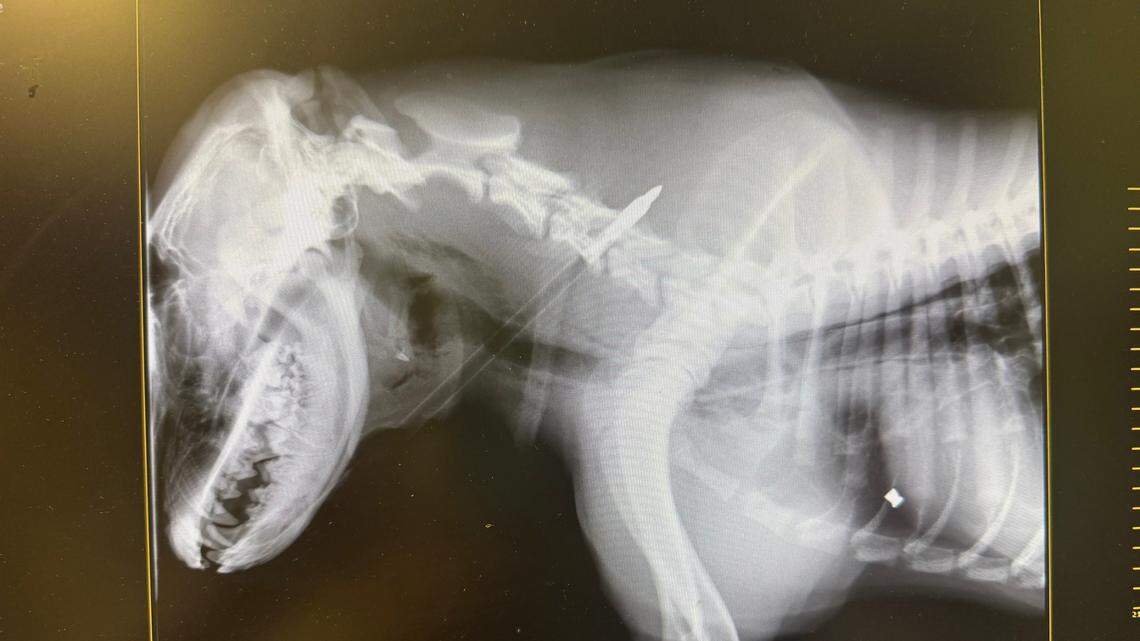

X-ray shows the arrow lodged in Lucky’s trachea.

X-ray shows the arrow lodged in Lucky’s trachea. Photo courtesy of Stray Rescue of St. Louis

“We got him settled and as comfortable as possible. In the background, you can hear anger in our staff members’ voices,” the shelter said. “Once we performed x-rays, we could clearly see that the arrow is going right through him. It is near his spine and esophagus. As if that wasn’t horrific enough, he also has a bullet lodged in his abdomen.

Since the arrow was stuck in his trachea, “Lucky Charm,” as he was named by the shelter workers, would have to be transported to a specialist for a difficult surgery.